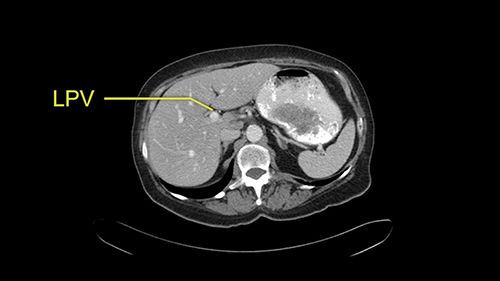

The third issue for this patient is that in Segment 7, I notice that there is intrahepatic ductal dilatation due to a small tumor causing obstruction. Now this tumor is not well-visualized on the most recent CT scan but I want to carefully evaluate the bile duct, where the obstruction is, so at the time of surgery I can be sure to remove the affected bile duct as well as the small tumor that is causing the ductal dilatation.

![[before chemo]](jpg/preop_aw_moment8.jpg)

So in light of the CT findings, the plan for this patient is a right hemihepatectomy that would encompass all the small tumors including the one in 4a-8, 5, 6-7; and the reason that I would do a full right hemihepatectomy is because of the intraductal dilatation in Segment 7 that makes me suspicious that there is a tumor that cannot be removed with simple wedge resections.

Divide bile duct in liver

My name is Steven Gallinger, I’m a professor of surgery at the University of Toronto and an HPB surgeon at the University Health Network. I’ve been asked to comment on this case and discuss preoperative planning, potential slowing down moments. It’s an interesting 65-year old woman with right sided colon cancer and synchronous liver metastases: small metastases in the right lobe of the liver and she had the primary tumor resected and then underwent neoadjuvant chemotherapy for her small liver metastases in Segments 4, 5, 6 and 7. The distribution of the metastases is interesting. They are small lesions, but the interesting additional feature is isolated segmental dilatation of the Segment 7 bile duct which suggests an intrabiliary metastasis somewhere near the origin of the main Segment 7 duct. Because I can trace it close to the porta [hepatis], I would assume that it’s pretty close to the bifurcation of the main right sided bile ducts but I can’t actually see the actual tumor. It’s really just presumptive.

She underwent neo-adjuvant chemotherapy and then had a series of additional investigations and the one that I’m focusing on in more finer detail is an MRI with Primovist and I’ve had the benefit of looking at the report. The main issues are in Segments 5,6, and 7. Three small metastases that remain and the radiologist also comments on the lack of biliary dilatation which was present before; implying that the intrabiliary metastasis somewhere at the origin of the Segment 7 duct, has regressed or been adequately well treated with chemotherapy. That’s probably where the difficult decision making comes in the OR. So from an oncologic point of view, I would plan for a right hepatic lobectomy. The rationale would be that this would include the more peripheral Segment 5, 6, 7 metastases that are obvious but also would take care of the presumed Segment 7 intrabiliary metastasis that does not actually visualize on any of the scans but is assumed to be there with evidence of the duct dilatation which then resolved. One could argue whether we should preserve liver and ignore that duct dilatation that was there before but I think my own preference would be to resect the right lobe and that would certainly include any residual disease in that Segment 7 bile duct and moreover, coming back to do a completion right hepatic lobectomy would be difficult particularly around the porta where this metastasis is presumably still there and even if its quite small.

Finally the bile duct is divided in the liver. I can actually see this patient’s bile duct. It’s a bit dilated and she had cholecystectomy. I think we would divide the bile duct in the liver. It’s hard to anticipate from a CT scan what you’re going to see because you can’t actually see the bile duct very well on the average CT.

![[Sg7 branch]](jpg/preop_sg_moment6.jpg)

So overall I would plan to do a right hepatic lobectomy. The slowing down moments are the usual ones: carefully mobilizing the right lobe, not injuring the main hepatic veins or the vena cava, the right portal vein split, the length of the right portal vein. The rest looks very routine. The oncologic issue I’ve already decided I’m going to do a right lobe with the assumption that there is an intrabiliary metastasis somewhere near the origin of the right- the Segment 7 duct and probably close to the bifurcation of the main right bile duct so the best way to get a margin is to actually divide the right bile duct close to its origin the way you would normally do a right hepatic lobectomy.